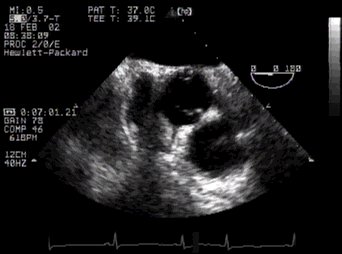

2. The following view is really rather important, mainly because it contains an unmistakable landmark - the 'Mercedes-Benz sign'of the aortic valve in cross section (av). Posterior to this valve (and close to the probe) you can see the left atrium, to the patient's right (your left) is the right atrium, and ventrally is the right ventricular outflow tract.

UP Basal aortic valve CLICK FOR VIDEO: aortic valve (basal)

MPG  MPG4  QT  Real

Note that the anatomical section is slightly off-true, so the sign is skewed - a useful tip! Note that in this fairly cephalad view, the interatrial septum is thick - more inferiorly it thins markedly. The right ventricular outflow tract is also well seen (rvot).